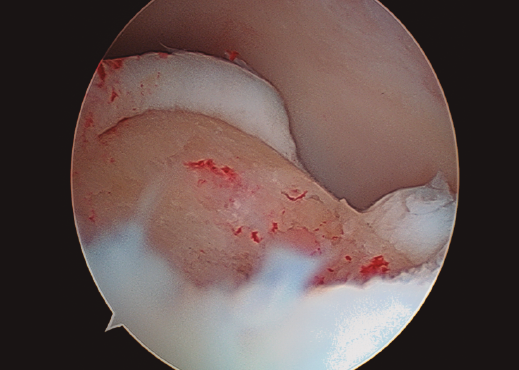

Figura 1. Lesión osteocondral de grado IIB en vertiente talar medial.

- Inicialmente procedemos a retirar el cartílago inestable, el hueso necrótico y la capa superior calcificada mediante un sinoviotomo, fresa motorizada, junto con instrumental de curetaje artroscópico (Figura 1).